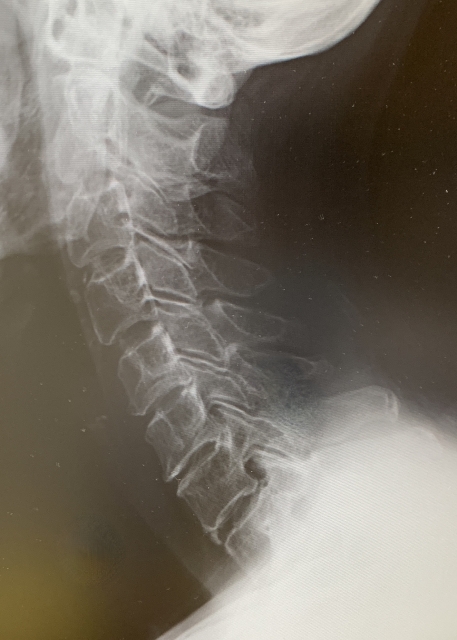

頚椎症とは、頚椎(首の骨)周辺の骨や椎間板、靱帯などが年齢とともに変性し、神経や脊髄を圧迫し、首の痛みや肩こり、腕や手のしびれ、力が入りにくいなどの症状が現れる病気です。特に中高年以降に多く見られ、長年の負担や姿勢の悪さ、加齢などが主な原因です。症状が軽い場合は、安静やストレッチ、理学療法で改善を図りますが、重症の場合は手術が考慮されることもあります。早期の対策や予防が大切な疾患です。

加齢による首の骨(頚椎)や椎間板の変性です。年齢を重ねることで椎間板の水分や弾力性が失われ、クッション機能が低下します。その結果として、骨のトゲ(骨棘)が形成されたり、靱帯が厚くなったりして神経や脊髄を圧迫します。さらに、長年の不良姿勢やデスクワーク、首への過度な負荷も頚椎症の発症リスクを高めます。また、遺伝的な体質やスポーツ、交通事故によるケガなども要因になることがあります。よって、複数の要素が重なり合って頚椎症は発症します。

主に40歳代以降で、椎間板の老化が起こり、水分量が減少して弾性がなくなります。加齢に伴って頚椎も変形し、脊柱管内や脊柱管から外にでる部分で神経根が圧迫されるようになることがあり、頚椎症といわれます。頚椎症に悩む方が快適に日常生活を送るには、首への過度な負担を避けることが大切です。首を急激に動かしたり、無理なストレッチ・マッサージを行ったりすることは控えます。また、長時間同じ姿勢で過ごすことや、高い枕や、やわらかすぎる寝具の使用も頚椎に負担をかけるため、注意が必要です。重いものを持つ際には身体全体を使い、急な動作や外傷にも気を配ります。首や肩に違和感、痛みがあるときは無理をせず、早めに医師に相談してください。日常から正しい姿勢を心がけることが再発予防のポイントです。